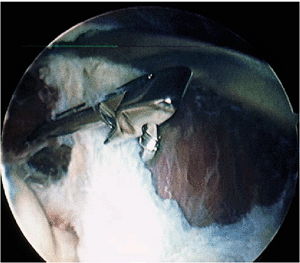

![]() |

Figure 2-17. A: Initial view of the lateral capsule in a patient with lateral epicondylitis. Note rent in capsule (arrow). B:

The angiofibrotic dysplasia or degenerative lesion of the tendon of the extensor carpi radialis brevis tendon or so-called Nirschl lesion as visualized arthroscopically. C: Excision of the lesion with a shaver placement during excision. D: Completed excision and abrasion of the lateral epicondyle. |

management of lateral epicondylitis. In these patients, concomitant

damage is also often noted to the capsule and to the posterolateral

aspect of the elbow. In this initial view, the fenestrations of the

capsule as a result of the chronic inflammation of lateral

epicondylitis may be noted (Fig. 2-17A). The

straight lateral portal is utilized to excise the capsule, allowing

visualization of extensor carpi radialis brevis tendon and the

contained Nirschl lesion (Fig. 2-17B). The shaver is then used to resect this lesion and abrade the bone (Fig. 2-17C).

Occasionally, a cautery device may be used to further elevate this area

and allow better access to the lateral epicondyle. Any concomitant

calcification should be removed as well. Once the entire degenerative

lesion has been excised and the epicondyle is abraded, the arthroscopic

portion of the procedure is completed (Fig. 2-17D).